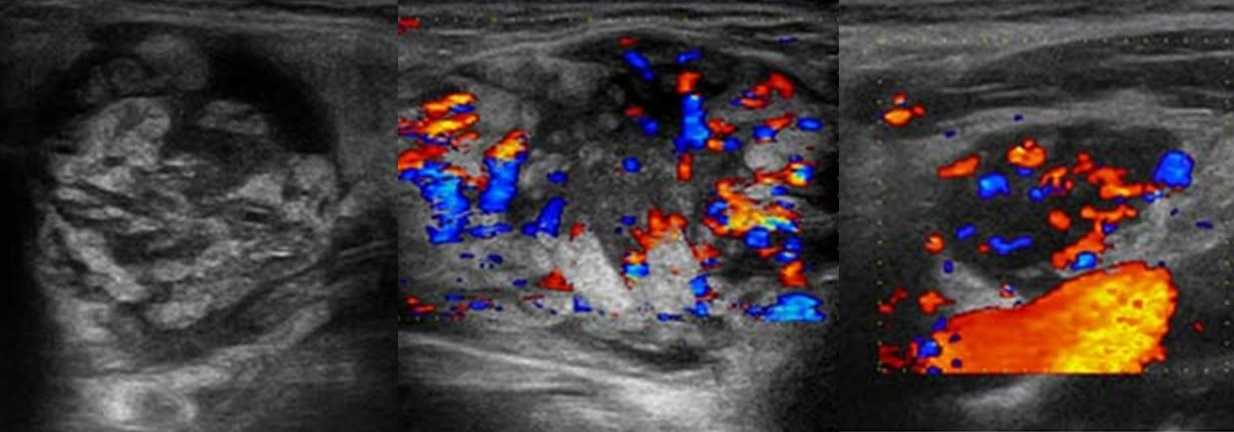

Туберкулез чаще поражает лимфоузлы шеи, подмышечной и паховой области. Обычно туберкулезный лимфаденит развивается медленно, лимфоузлы безболезненные, средний размер 3 см, но иногда могут достигать 10 см. На УЗИ пораженные лимфоузлы увеличены, гипоэхогенные, с нечетким контуром, часто можно увидеть выраженный периаденит и спаянные пакеты лимфоузлов. Для туберкулезного лимфаденита характерна неоднородная эхоструктура — анэхогенные кистозные полости и кальцинаты. При прогрессировании заболевания может образоваться абсцесс и свищи.

Рисунок. На УЗИ на шее определяется группа увеличенных лимфоузлов, неправильной формы; эхогенность понижена, центральный рубчик отсутствует; неоднородные за счет анэхогенных аваскулярных зон — очаги некроза; кровоток усилен, ход сосудов неправильный, выраженный подкапсульный кровоток. Заключение по результатам биопсии: Туберкулез лимфоузлов.

Рисунок. На УЗИ увеличенные лимфоузлы, неправильной формы с размытыми границами; эхогенность пониженная, центральный рубчик отсутствует; неоднородные за счет мелких кистозных полостей и гиперэхогенных включений с акустической тенью позади (кальцинаты). Заключение по результатам биопсии: Поражение лимфоузлов атипичными микобактериями. Гистологически очаги инфекции М. tuberculosis и атипичных микобактерий часто неразличимы. Классическим морфологическим проявлением в обоих случаях служит гранулема с казеозным некрозом.